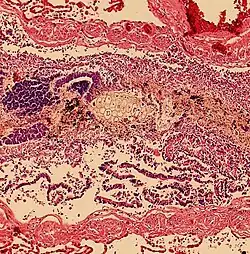

Histopathology of aspiration, taken from an autopsy, showing plant-like cells in a bronchiole. However, alveoli were clear, indicating a finding secondary to cardiopulmonary resuscitation rather than a primary cause of death.

Aspiration can result in patient death through a variety of mechanisms. It is important to recognize and diagnose early in order to improve patient outcomes. Death from aspiration and aspiration-related syndromes is most common in elderly patients with known baseline risk factors, though it frequently goes unrecognized.[18]